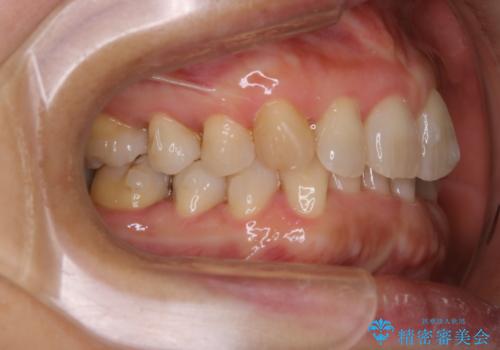

- 上下の歯のがたつきと、噛み合わせが深いことを気にされてご相談にいらした方です。噛み合わせに参加していない歯を抜歯してインビザラインにて治療を行いました。

一般的に噛み合わせの深い方へのインビザライン治療は適応が難しいとされていますが、今回は噛む力を上手にコントロールできたことと、内側に入り込んでいた前歯の角度を調整したことで下の歯がしっかり見えるようになりました。短期間で劇的に見た目が改善し、大変喜んでいただけました。